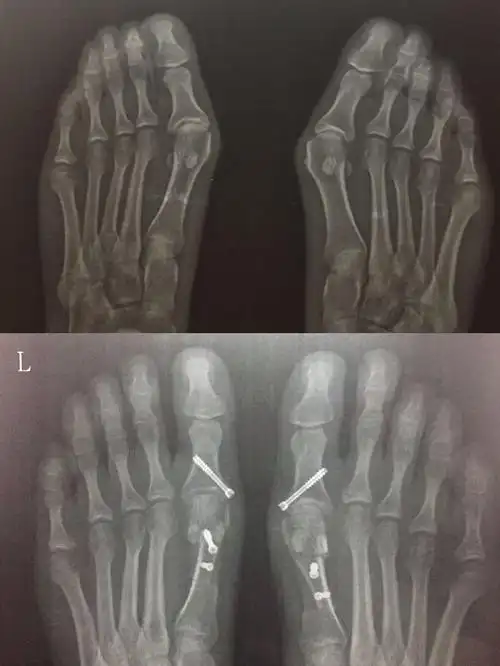

36岁双足拇外翻畸形矫正手术一例

图片尺寸4729x5717